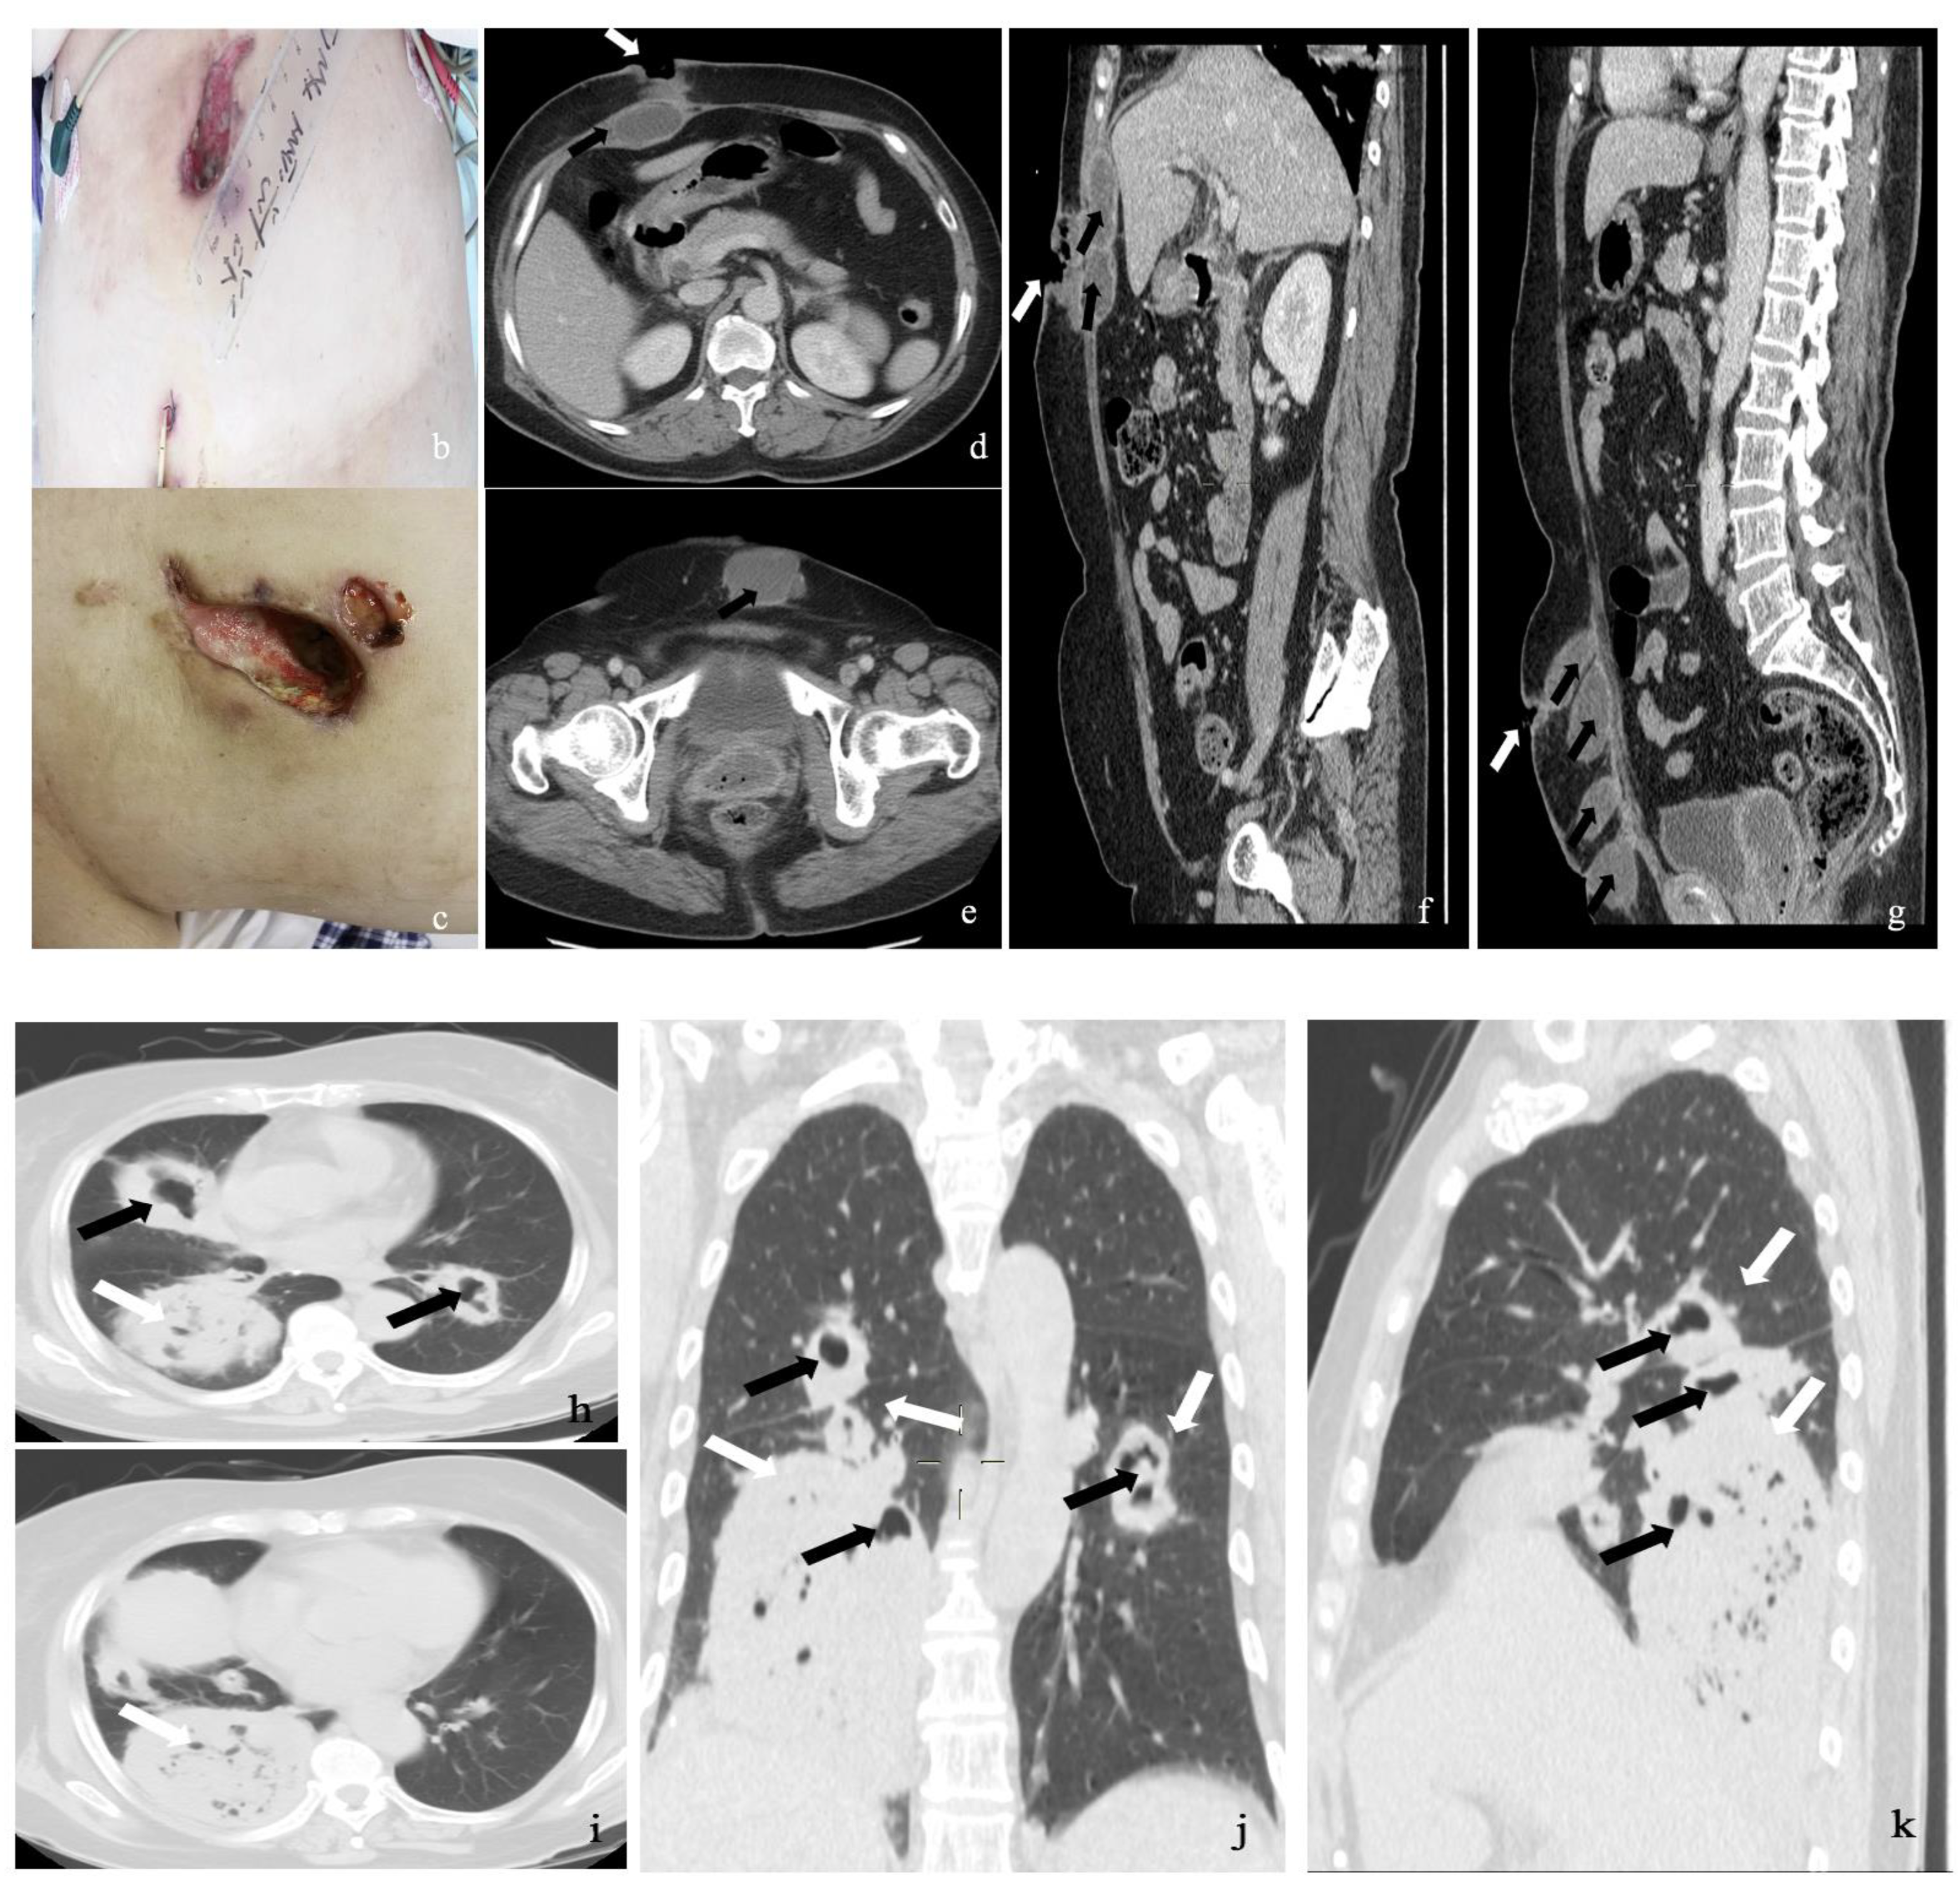

2.1. Case 1

2.2. Case 2